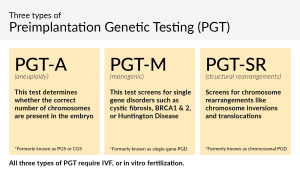

Step 5: What Happens to the Eggs After?

What Happens?

Once the eggs are out, they head straight to the lab. Scientists check them under a microscope to see how many are mature (ready to fertilize). Then, they mix them with sperm—either naturally or by injecting one sperm into each egg (called ICSI)—and wait to see if embryos form.

Cool Tidbit

Not every egg makes the cut. On average, only about 70% are mature enough to use. It’s like auditioning for a play—some eggs just don’t get the part!